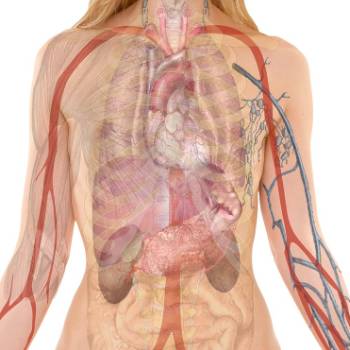

갑자기 살이 빠지는 이유 5. 심부전

심부전은 심장이 혈액을 효과적으로 펌프질 하지 못하는 상태로, 체중 감소를 초래할 수 있습니다. 심부전 환자들은 종종 피로감과 호흡 곤란을 경험하며, 이는 식욕 부진과 체중 감소를 유발합니다. 또한, 심부전은 소화기 계통에 영향을 미쳐 음식의 흡수를 방해할 수 있습니다. 체중 감소는 심부전의 심각성을 반영하는 지표로 사용될 수 있습니다.